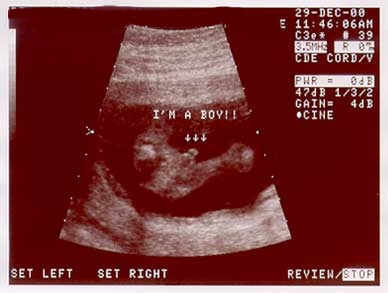

These images show the baby at 17wks. (Dec. 29, 2000) |

Image sequence 1 of 3 |